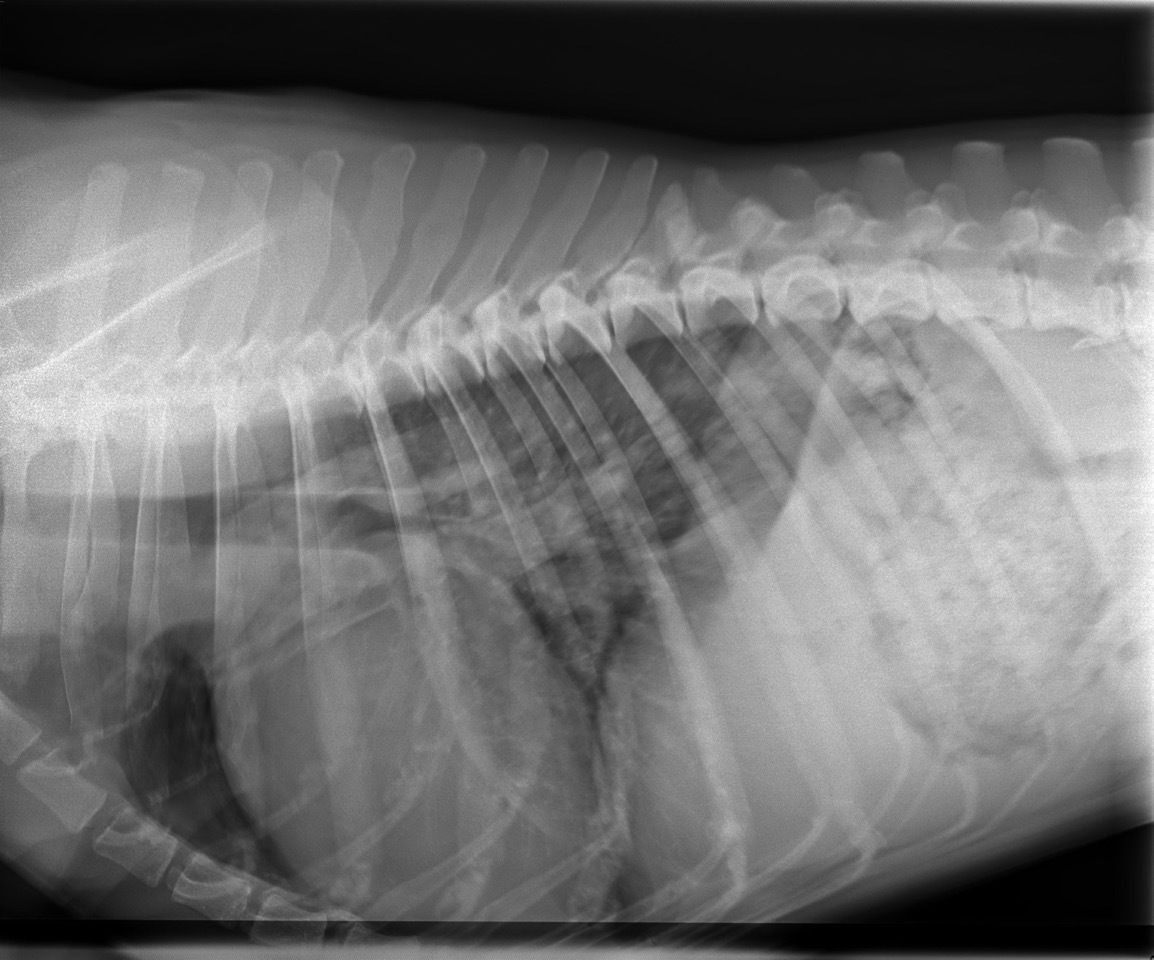

Außerdem habe ich eine Röntgenaufnahme von Momos Brustkorb angefertigt. Diese zeigte dann auch eine Verschattung der hinteren Lungenlappen. Die Herzsilhouette war vergrößert und es war eine Stauung der Lungenvenen zu erkennen, was auf ein kardial bedingtes Lungenödem schließen lässt. Es befand sich also Wasser in Momos Lunge.

Auf eine antiarrhythmische Therapie habe ich zunächst verzichtet, denn ich wollte zunächst die Wirkung der genannten Medikamente abwarten. Bei der Kontrolluntersuchung eine Woche später war Momo dann auch wieder deutlich fitter und zeigte keinen Husten mehr. Im Röntgen war auch kein Lungenödem mehr zu erkennen. Und auch die Arrhythmie war nicht mehr nachweisbar. Ich konnte also die Dosierung des entwässernden Medikamentes reduzieren – natürlich unter Kontrolle der Atemfrequenz. Generell rate ich in solchen Fällen zu regelmäßigen Kontrollen im Abstand von ungefähr drei Monaten – so auch bei Momo.

Zwei Monate später folgte dann ein kleiner Schreck - Momo erschien erneut wegen Husten in unserer Praxis. Doch jetzt war der Rachen verschleimt, die Halslymphknoten waren vergrößert und Husten war durch Druck auf den Kehlkopf auslösbar. Die Röntgenaufnahme des Brustkorbes zeigte keine Verschattung der Lunge. Damit war klar, dass der Husten dieses Mal nicht durch die DCM verursacht wurde, sondern durch eine Infektion der oberen Atemwege. Diese „normale Erkältung“ konnte schnell durch Gabe von Hustensaft und Schleimlöser unter Kontrolle gebracht werden.